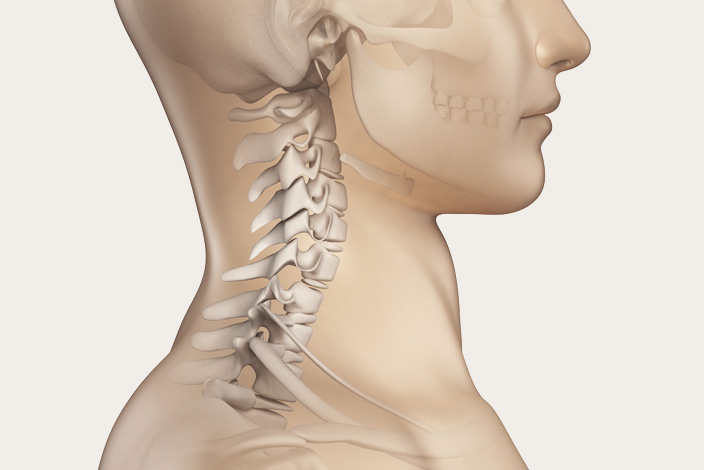

우선 목디스크란 목뼈 사이의 디스크가 깨지거나 상해 일어나는 질환을 의미합니다. 디스크는 척추뼈 사이에서 충격을 흡수하고 신경을 보호해주는 역할을 하는데, 디스크가 손상되면 신경이 압박되어 통증, 저림, 마비 등의 증상이 보여집니다.

우리의 목은 인체에서 무척 요긴한 역할을 합니다. 머리를 지지하여 돕고, 머리를 움직여 시야를 확보하는 역할을 히며, 척추의 시작 부분으로서 척추를 지켜주고, 척추를 통해 뇌와 인체의 다른 부분으로 신경을 보급하는 역할을 합니다.